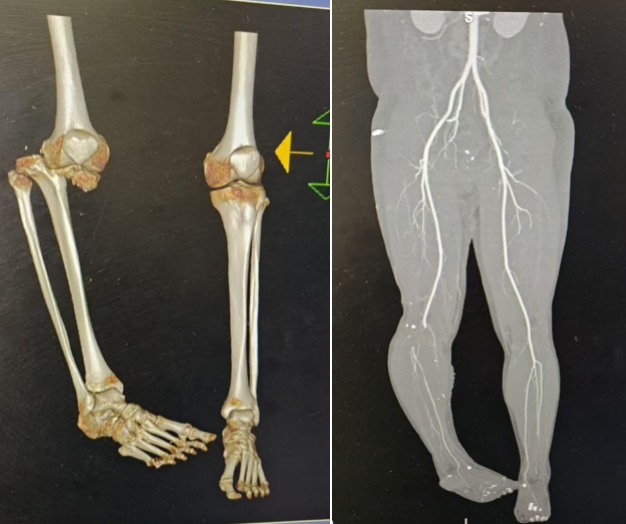

患者到达崂山院区后进行了CTA检查,进一步明确了术前的初步判断,即小腿“生死存亡”的主要动脉——腘动脉有一段已发生断裂,且膝关节脱位,腘窝处神经损伤,伤口污染严重,足部、踝关节也存在多发创面和骨折。由于两院区在患者就诊后进行了快速有效的沟通,为患者赢得了大肢体再植宝贵的“黄金6小时”。也是经过6个小时的奋战,手足显微外科值班医师吴彩风、汪健在麻醉科及手术室医护团队的密切配合下,按照既定方案为患者成功实施再植保肢手术,顺利度过危险期。